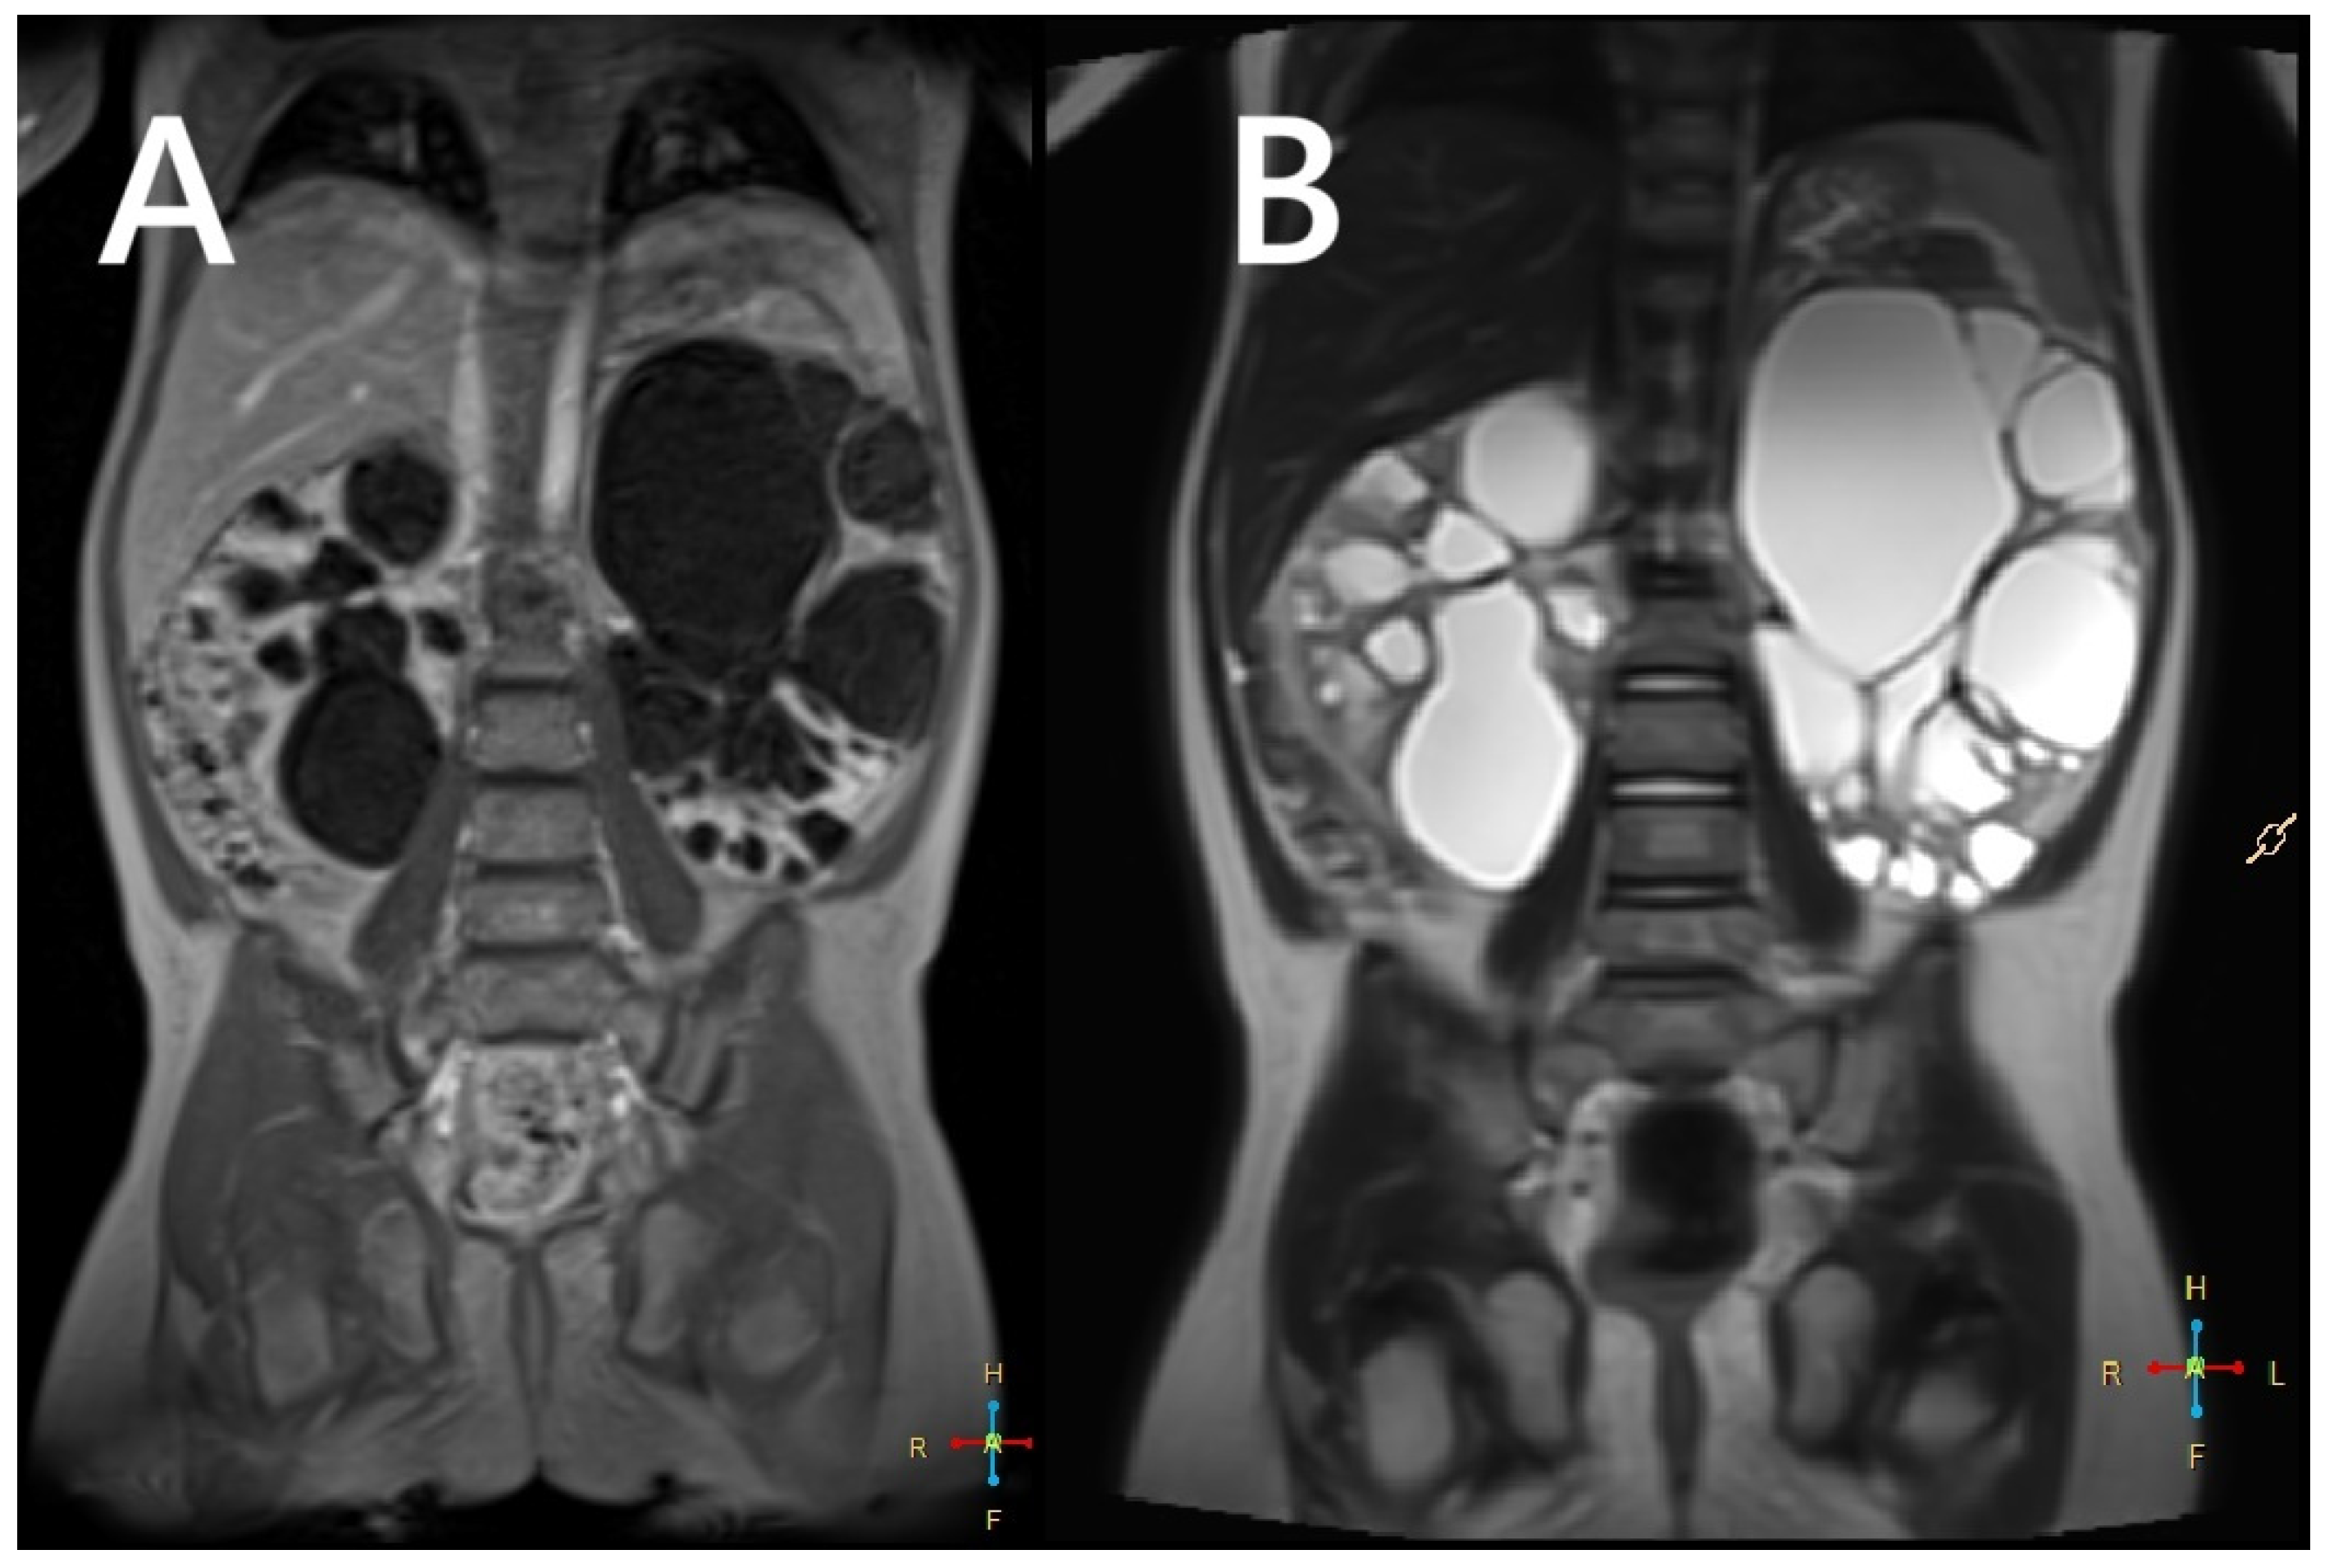

Renal involvement in children with TSC is estimated to occur in approximately 80% of cases. The most common kidney manifestations are angiomyolipomas (70–80%) and cysts (around 50%), presented in Figure 1. Other tumors, including RCC or renal oncocytoma, are less common (<2%) [12,13,14].

Figure 1. Ultrasound (A) and MRI (B) images of a 16-year-old boy. The ultrasound reveals numerous hyperechoic lesions, consistent with AMLs, along with several cysts (A). MRI shows large focal lesions (arrows), most likely representing atypical AMLs (B).